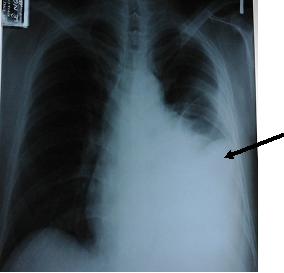

- Hình ảnh XQ tim phổi thẳng lúc chưa chọc dịch.

Hình 1. Hình ảnh XQ tim phổi lúc bệnh nhân chưa được chọc dịch màng phổi: tràn dịch màng phổi trái số lượng nhiều, gây xẹp phổi trái (mũi tên)